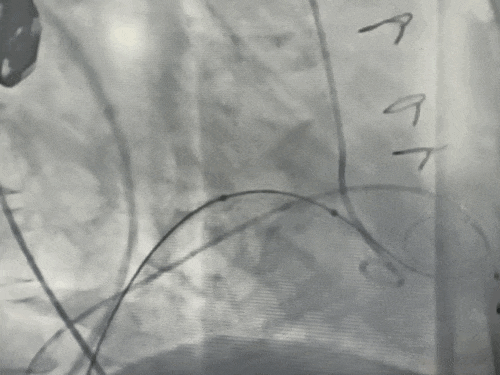

经左股动脉送入猪尾导管至左心室。在快速心室起搏下,使用14×40 mm球囊对衰败的二尖瓣生物瓣进行预扩张,同期行左室造影评估,判断新瓣膜植入后发生左室流出道梗阻的风险较低。

4.瓣膜植入:

将25#球囊扩张式瓣膜输送系统沿加硬导丝送至二尖瓣环位置。在TEE及DSA多角度共同确认下,精确定位。在RVP下,快速充盈球囊,将新瓣膜成功释放并固定于原生物瓣环内。即刻TEE及造影评估显示:人工瓣膜位置良好,功能正常,未见瓣周漏,左室流出道通畅。